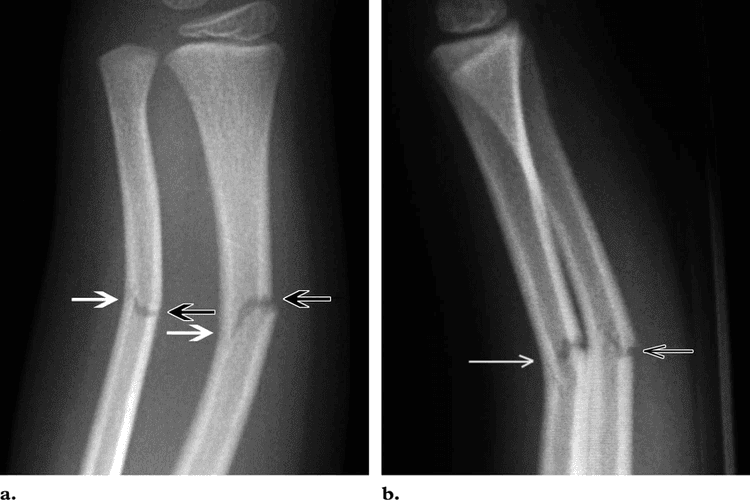

Greenstick Fracture - एका बाजूने फ्रॅक्चर, पण हाड वाकल्याने ते पूर्ण न तुटणे. हे फ्रॅक्चर लहान मुलांमध्ये जास्त आढळून येते कारण त्यांची हाडे लवचिक असतात.

Torus Fracture - यात हाड तुटत नाही पण हाडाचा आकार बदलल्याने वेदना होतात.